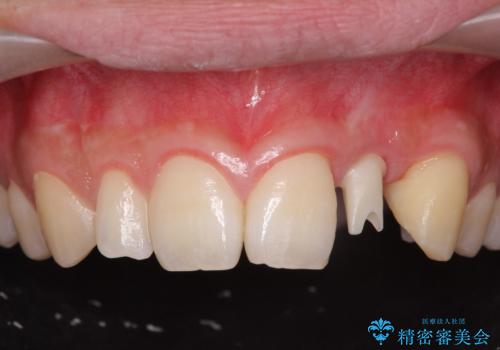

- 前歯の永久歯が元々なく、乳歯を失ったタイミングで前歯の審美性の回復を求めて来院されました。

機能・審美性の回復手段として、インプラント治療・ブリッジ・部分床義歯が考えられます。

それぞれの治療に特徴がありますが、取り外しの必要がなく隣の歯を削る必要も必要ないインプラント治療を選択されました。

前歯部にインプラントを埋入し、きれいに仕上げるためには骨の造成技術や歯肉の厚みを増すような処置を行い、インプラント周囲の環境を整備することが肝要です。